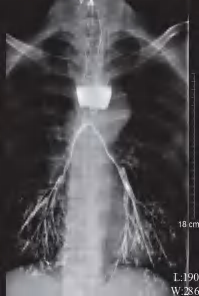

例如,当超长食管癌发展为侵穿胸主动脉,引起食管胸主动脉瘘,引发大出血,患者会立即毙命,所以凶险指数排第1位。笔者曾收治一位患者,本来1个月前准备手术,后因私事推迟手术。结果患者在第二次正电子发射计算机断层显像(PET-CT)检查5天后因食管气管瘘死亡(图1-3)。

图1-3 超长食管癌患者癌肿侵穿支气管的食管造影表现